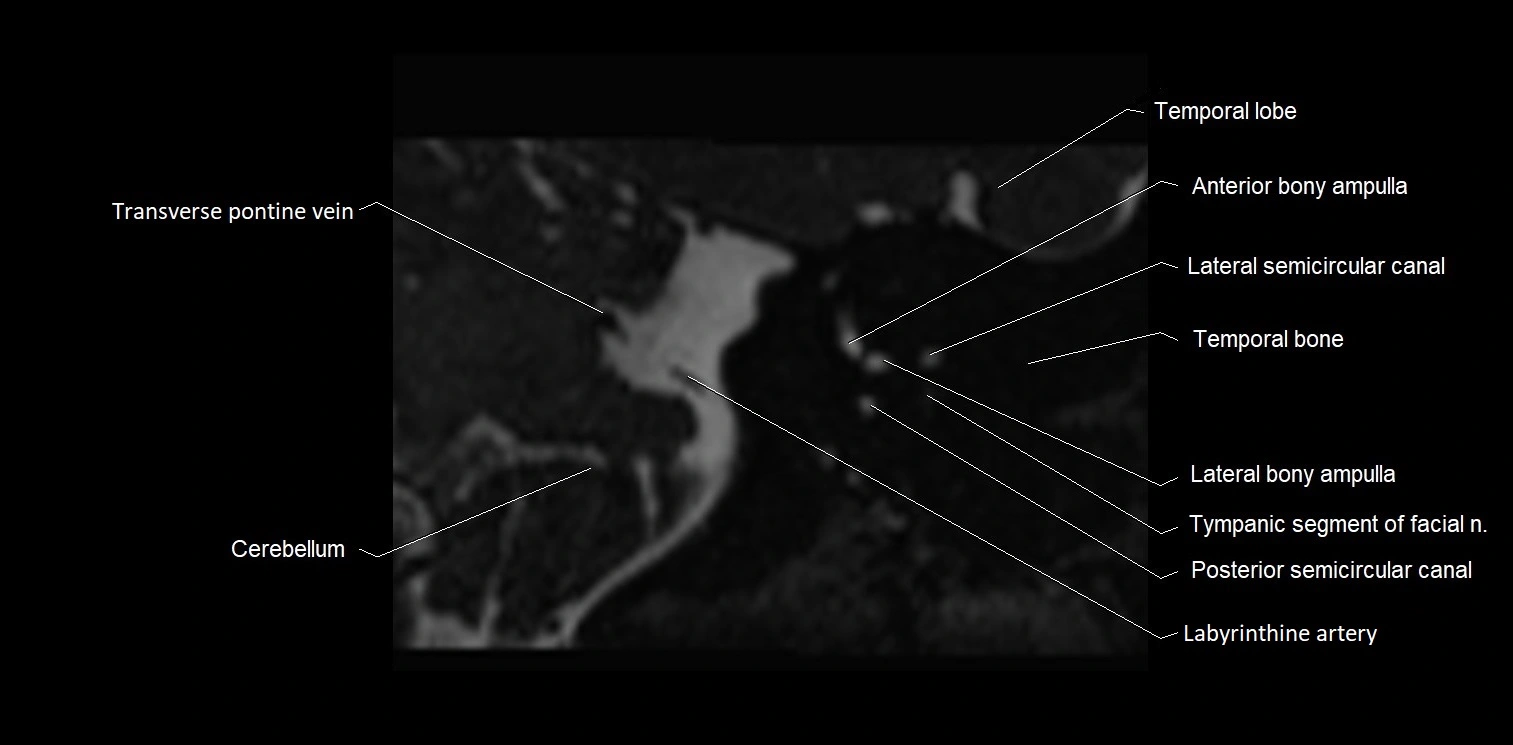

MRI images

image